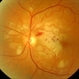

- Purtscher's retinopathy

- Fundus images of a 21-year-old woman with Purtscher's retinopathy. Mild visual improvement 20/200 OU vs. 20/400 OU .